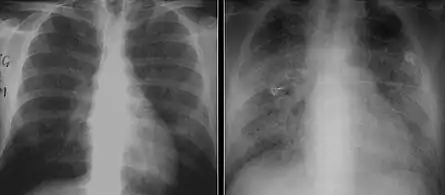

The diagnosis can be confirmed by the characteristic appearance of the chest X-ray and an arterial oxygen level (PaO2) that is strikingly lower than would be expected from symptoms. Gallium 67 scans are also useful in the diagnosis. They are abnormal in about 90% of cases and are often positive before the chest X-ray becomes abnormal. Chest X-ray typically shows widespread pulmonary infiltrates. CT scan may show pulmonary cysts (not to be confused with the cyst-forms of the pathogen).

Chest X-ray of increased opacification (whiteness) in the lower lungs.

These chest radiographs are of two patients. Both show ground glass opacities. The left X-ray shows a much more subtle ground-glass appearance while the right X-ray shows a much more gross ground-glass appearance mimicking pulmonary edema.[7]